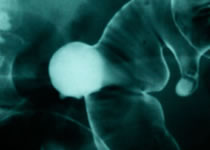

Gastroenterología

•Colonoscopia

•Cpre

•Videoendoscopía